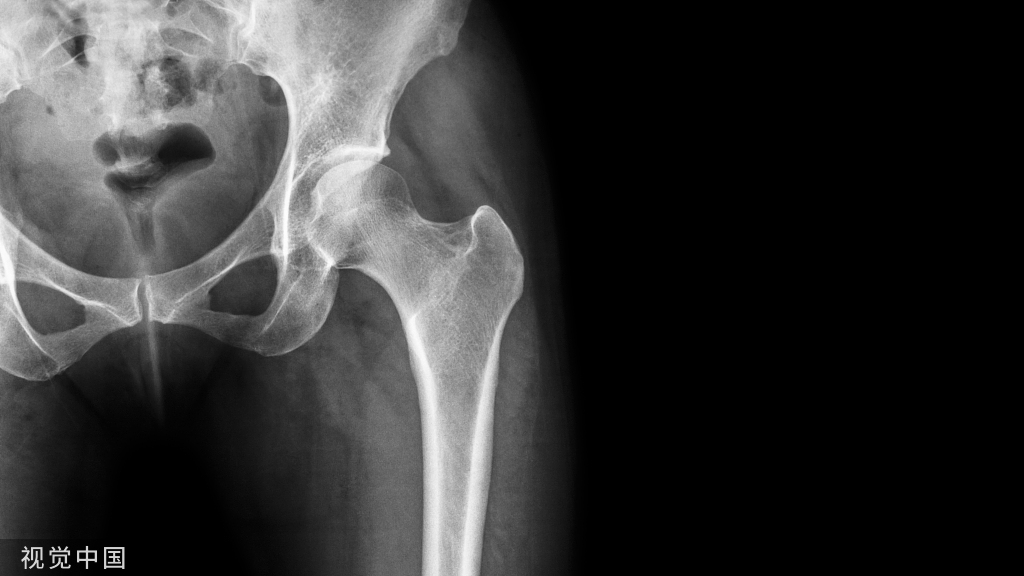

髋部骨折是老年患者常见的外伤性疾病。随着社会的发展,人类寿命的延长,人口老龄化已成为必然趋势,老年髋部骨折患者的数量日益增加,这类患者的围术期管理也将面临更加严峻的考验。

髋部骨折类型

不同类型的髋部骨折手术方式不同,造成的组织创伤不同,导致的术后疼痛也有一定的差异。